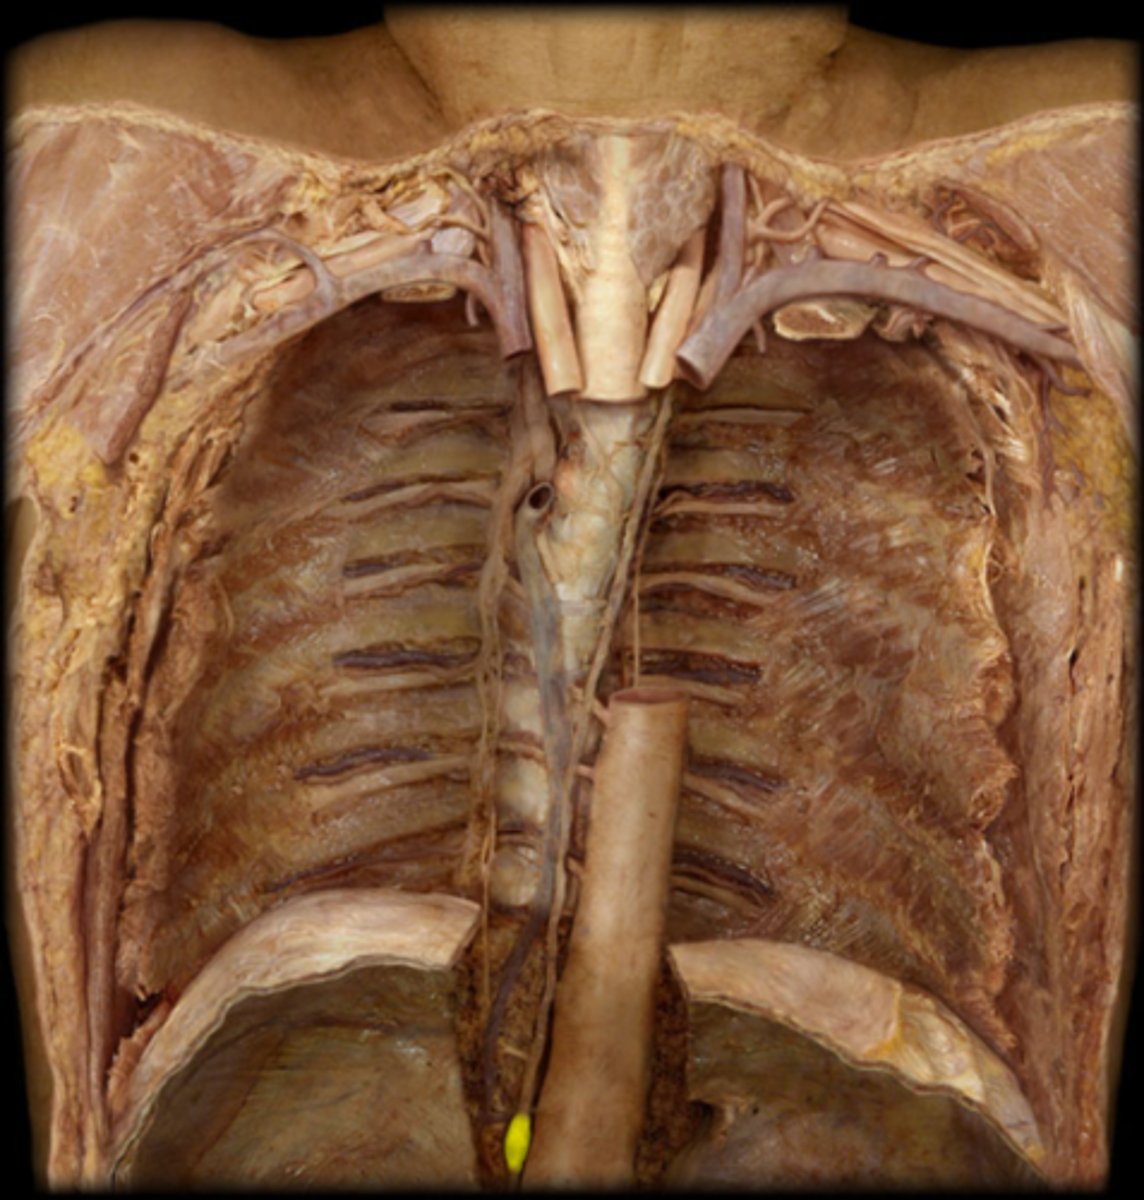

thoracic duct